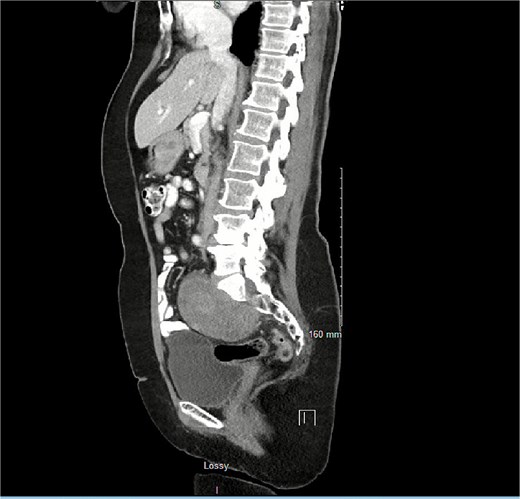

Given the frequency of her diverticulitis, she was interested in a laparoscopic sigmoidectomy. On entry into the abdomen, it was evident that the mass had enlarged and was juxtaposing the plane, which the medial to lateral dissection would occur (Fig. 2). Neurosurgery was called in intraoperatively, and it was decided that it would be best to perform this case with vascular surgery, neurosurgery, and colorectal surgery on a later date with an open approach.

Proximity of schwannoma to rectosigmoid junction on saggital view on repeat scan months later.